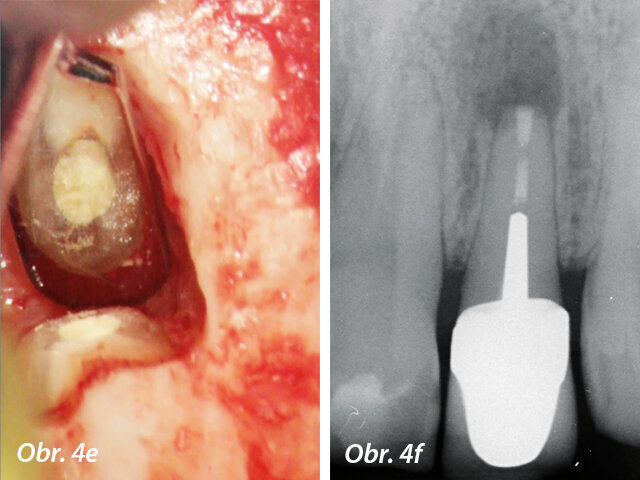

MTA má nejpříznivější výsledky jako materiál pro apikální chirurgii. Signifikantně vykazuje méně zánětlivých reakcí, podporuje tvorbu terciálního cementu a regeneraci periapikálních tkání (Torabinejad a Chivian 1999) (obr. 4a–f).

Předoperační RTG s velkým periradikulárním nálezem a periapikální chirurgie

Aplikace PD MAP White pomocí MAP systému a kondenzace MTA pluggerem

Pohled přes zrcátko - MTA výplň v apikální části a postoperační RTG s apikální výplní